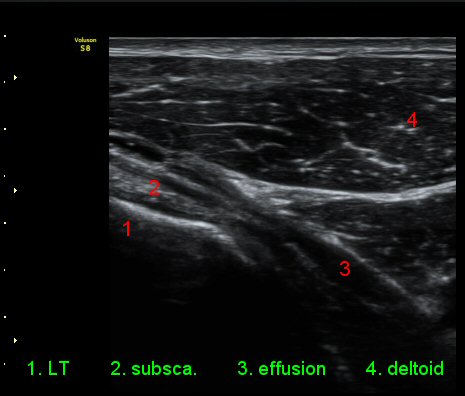

ŽÃËÀÚ¸¦ ¿À±¸µ¹±â ¾Æ·¡·Î ±æ°Ô ´ë°í °üÂûÇÏ´Ï ¿À±¸µ¹±â ¾Æ·¡, ¼ÒÈä±Ù ½ÉÃø¿¡ ¼ö¾×Àú·ù°¡

°üÂûµÇ¾î ¿À±¸µ¹±âÇÏÁ¡¾×³¶¿°À» ½Ã»çÇÑ´Ù(»çÁø 5).